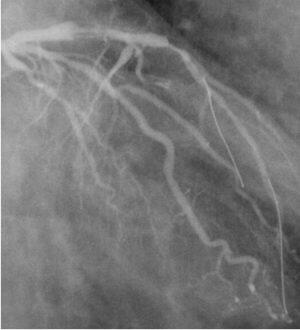

添付したイメージのようにLCX distalのtotal? subtotal?という病変(図:

pre_02s.jpg)に対しmini-ContrastでPCIしました。Wireは通ったんですがガイ

ドから造影するには造影剤がもったいないし、当然IVUSはテルモにしてdistalか

らチェックをしていますがそれでも本当のdistalは見えないし、マイクロカテか

ら造影するにはワイヤを抜かないとダメだし。。。

そこでハタと気がつきました。マルファンがあるじゃないか!!!

で、マルチファンクションから造影したイメージが pst_1MFs.jpg です。ほぼ

1mlの造影剤使用ですがかなりよく造影されているのが分かると思います。内腔

が若干太め?のためか造影効果はかなりいいです。当然ワイヤを抜かなくていい

のでそれも最高。

で、最終造影は pst_2GCs.jpg です。マルファン造影の質がいいのが分かると思

います。

ちなみにマルファン造影+IVUS+マーカワイヤ、でLCX13のsubtotal-total(結

局WhisperMSで通ったのでsubtotalか?)をあけて、LAD8にCypher入れて、造影

剤使用は23mlでした。